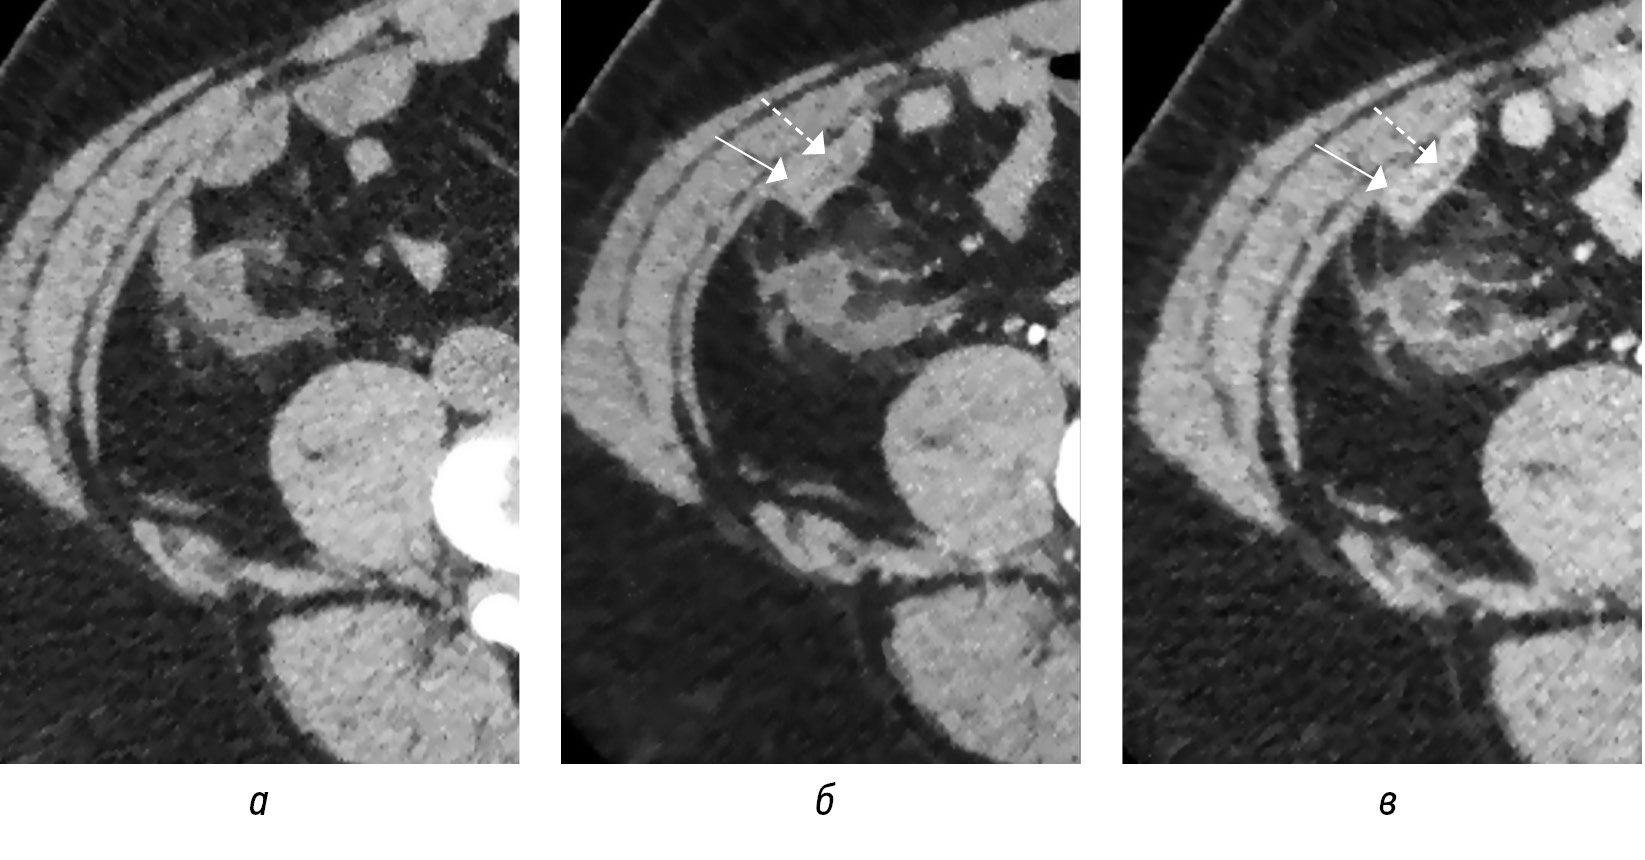

Диаметр аппендикса суммарно представлен содержимым и стенками аппендикса. При нативной КТ не всегда удается дифференцировать стенки от содержимого, необходимо введение контрастного вещества (рис. 2), в то время как при высокочастотном УЗИ возможно дифференцировать слои стенки аппендикса, наиболее информативен срез по короткой оси отростка (рис. 3, а, б). Во всех источниках утолщением стенок аппендикса считается толщина более 2 мм. Только при УЗИ возможно определить несжимаемость при компрессии аппендикса, что является важным признаком острого воспаления [18].

Рис. 2. КТ-изображения в аксиальной плоскости в нативную (а), артериальную (б), портовенозную (в) фазы демонстрируют (б, в) накопление контрастного вещества стенкой аппендикулярного отростка (стрелка) с более четкой дифференцировкой стенок от содержимого в просвете аппендикса (пунктирная стрелка)

Fig. 2. CT images in the axial plane in the native phase (a), arterial phase (б), portovenous phase (в) demonstrate (б, в) the accumulation of contrast agent by the wall of the appendicular process (arrow) with a clearer differentiation of the walls from the contents in the lumen of the appendix (dotted arrow)

Рис. 3. Сонограммы воспаленного аппендикса (стрелки) в В-режиме по короткой (а) и длинной (б) осям

Fig. 3. Sonograms of the inflamed appendix (arrows) in B-mode on the short axis (а) and on the long axis (б)